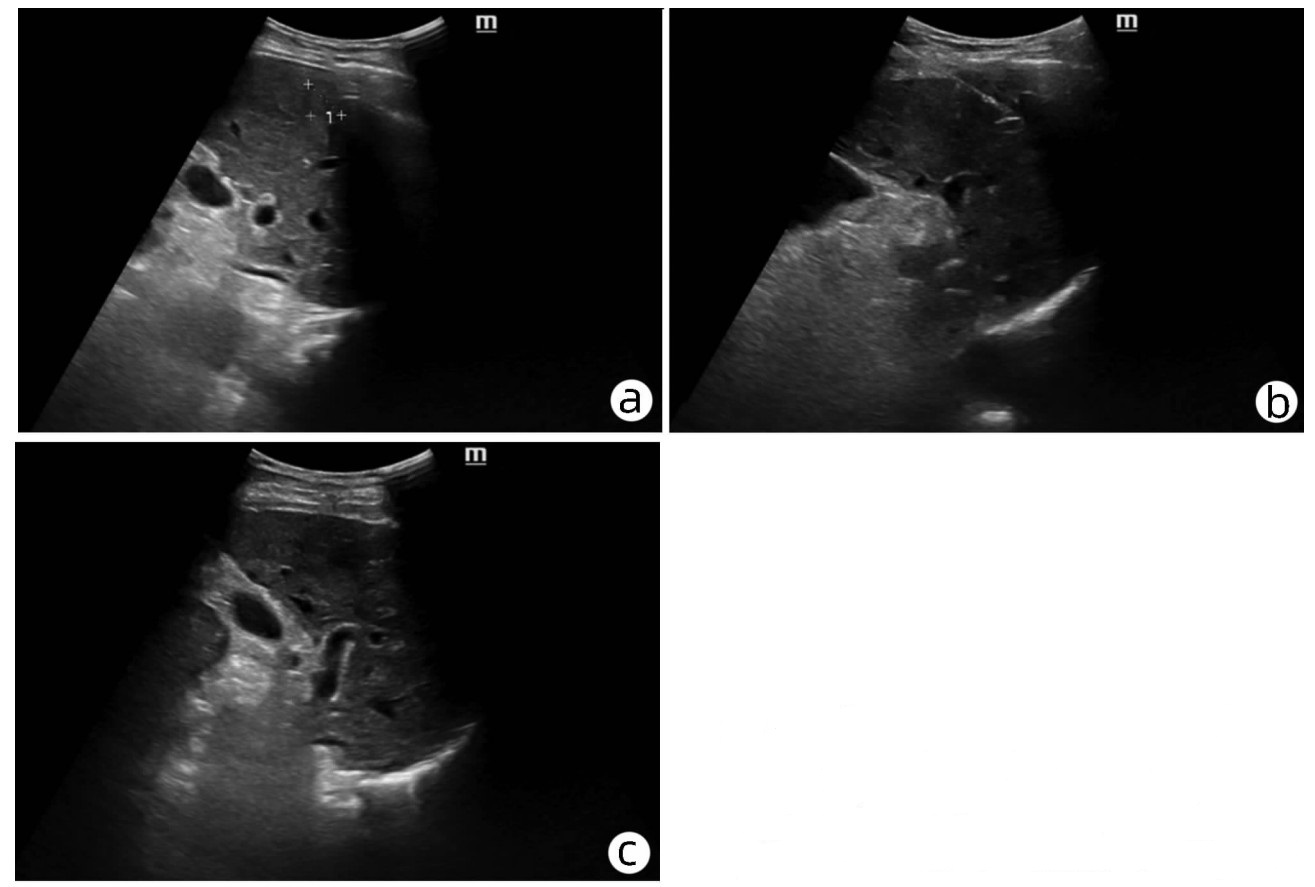

10例儿童肝糖原累积病临床及病理学分析

赵素贤, 刘世恒, 李文聪, 韩芳, 刘树红, 张庆山, 任伟光, 孔令波, 付娜, 王荣琦, 孔丽, 南月敏, 赵景民

2022, 38(8): 1839-1842. DOI: 10.3969/j.issn.1001-5256.2022.08.022

摘要(1409) HTML (513) PDF (2394KB)(109)

摘要:

目的  探讨儿童糖原累积病(GSD)的临床及病理学特点。  方法  选择2002年1月—2022年1月河北医科大学第三医院及解放军第五医学中心经病史、肝脏生化及肝活组织检查确诊的GSD 10例,对比分析人群特征、临床表现、生化指标、肝组织病理学特点。  结果  10例患儿发育迟缓,矮小,均表现为肝功能异常,轻度乏力、纳差、尿黄、眼黄,4例患者肝脾肿大。6例患者有低血糖的临床表现;1例患儿双侧腓肠肌肥大,Gower征阳性。2例患儿巨细胞病毒IgG阳性。肝组织病理学表现肝细胞弥漫性肿大,胞浆空淡,核小居中似植物细胞状,伴或不伴纤维组织增生。  结论  GSD患者多数有发育迟缓、转氨酶异常,肝组织病理检查有其特异性病理特征。